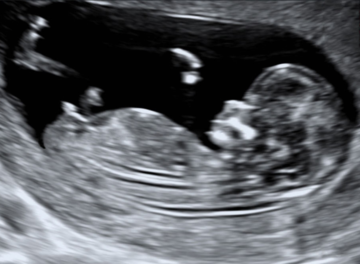

Nuchal translucency

The optimal gestational age for measurement of fetal NT is 11+0 to 13+6 weeks. The minimum fetal crown–rump length (CRL) should be 45 mm and the maximum 84 mm.